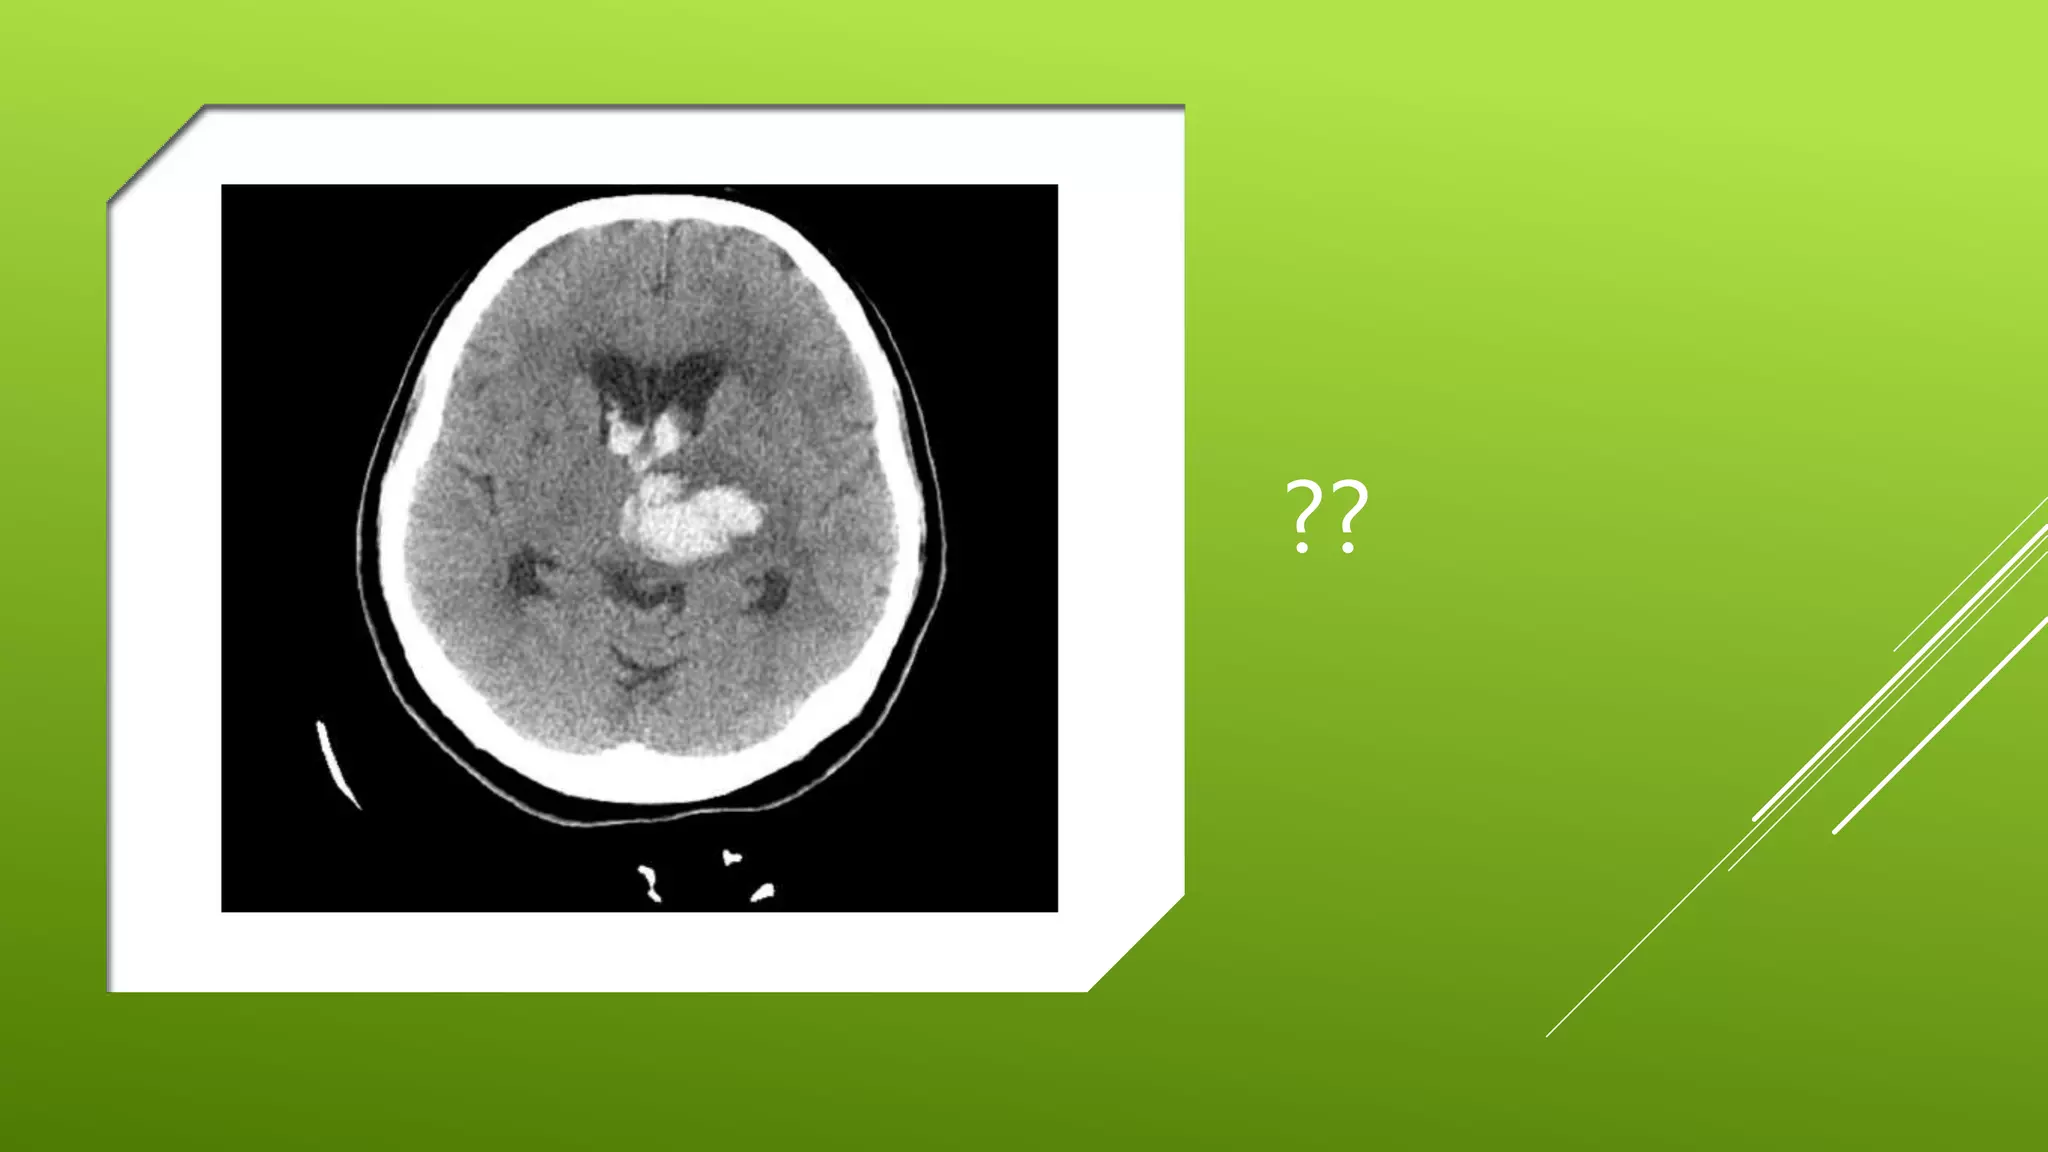

This document contains a series of radiology-related questions and prompts seeking identification and interpretation of various imaging findings, patient presentation details, monitoring values, scoring systems, diagnoses, and management steps. Specific topics include identifying x-ray and CT scan findings, interpreting EKG results, recognizing arrhythmias, assessing intubated and post-surgery patients, and evaluating compliance with treatment plans.